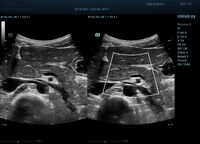

HD Scope позволяет достигать поразительной разрешающей способности выбранной зоны сканирования, при этом улучшая как детализацию, так и контрастность изображения. Помимо пространственного разрешения мы получаем преимущество и по разрешению во времени. Прибор получает огромное количество нативных изображений практически одновременно, и при сборе итоговой картины не происходит смещения объекта под датчиком, а значит и нет размывания изображения. Все участки раздела фаз, каждый контур образования теперь видны, мы все ближе к идеальной картинке.